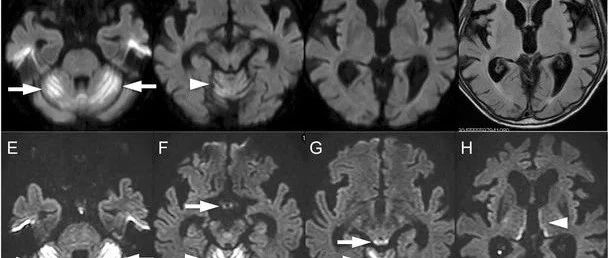

73岁男性,表现为进行性共济失调步态3周。其有3年的多发性骨髓瘤病史,接受了2年的化疗。1月前开始来那度胺(lenalidomide)治疗,出现过化疗相关的恶心和呕吐。否认习惯性饮酒史。MRI可见小脑半球和蚓部DW高信号病变(图1a-c)。FLAIR序列可见额叶和颞叶皮质萎缩,但幕上脑实质未发现异常病变(图1d)。患者从当地医院转来,主要表现为明显的平衡障碍,无法站立。神经系统查体提示双侧侧向凝视麻痹,双侧水平方向眼球震颤,深腱反射减退,共济失调性构音障碍和小脑性共济失调。在第一次MRI检查后两天,复查DWI可见小脑半球和蚓部,乳头,中脑顶盖和丘脑内侧病变(图1e-h)。患者小脑病变先于其他病变出现。FLAIR在相同区域也可见异常,增强后可见顶盖病变强化。脑脊液生化等结果正常。...